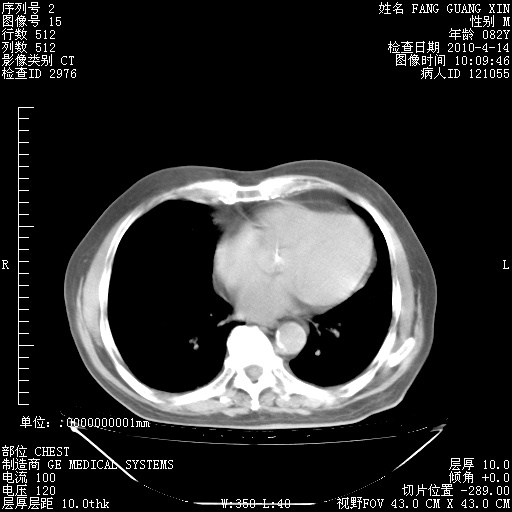

4月14日肺部CT